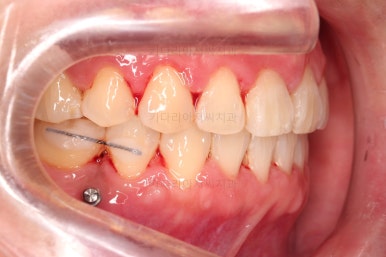

1. 초진

초진 시 입안의 모습입니다.

당장 눈에 띄는 부분은 아래 앞니 사이에 틈새가 있어 치석도 많이 쌓여있는 상황이고요.

윗니-아랫니를 각각 보면 치아가 썩고 부러져 뿌리만 남은 치아가 많이 보입니다.

남은 치아들도 곳곳에 충치가 보이고요.

또 전반적으로 앞니가 앞으로 밀려나와 뻐드러져 있는 모습도 관찰되네요.